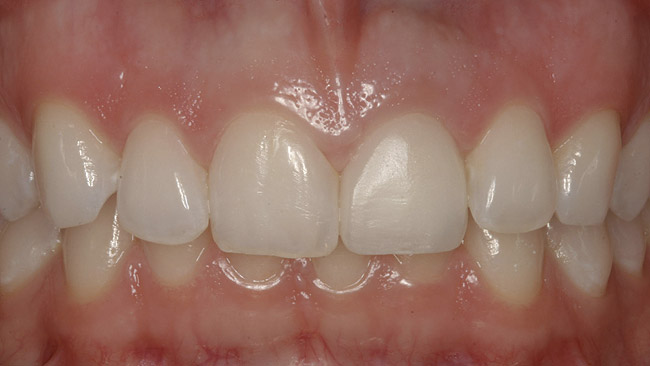

Figure 7  Finished feldspathic crowns, teeth Nos. 22, 23, 27, 28, and implant sites 24 through 26 showing good gingival emergence profile—post-cementation facial view.

Figure 7

Figure 8  Full smile—finished feldspathic crowns on teeth Nos. 22, 23, 27, and 28; implant crowns in sites 24 through 26; esthetic harmonization with opposing dentition.

Figure 8

After the zirconia abutments were torqued to 20 Ncm, cotton and composite were used to cover the screw access openings. Figure 7 and Figure 8 show the finished feldspathic porcelain crowns on implants in sites Nos. 24 through 26, and on teeth Nos. 22, 23, 27, and 28; all crowns were cemented with dual-cure resin cement. Good remodeling of gingival architecture is also apparent in Figure 7. As predicted, the free gingival margin (FGM) on No. 23 is approximately 2 mm coronal to those of the adjacent implant crowns on Nos. 24 through 26 (Figure 7); as per the patient’s initial statement, this discrepancy was not an esthetic concern to her. Figure 9 shows the final post-restoration periapical view.

This patient faced a unique situation, perhaps not previously reported: retaining a healthy mandibular lateral incisor knowing this would create an esthetic compromise. Indeed, while the discrepancy in gingival-margin height is noticeable in retracted view (Figure 7), it does not show in full smile (Figure 8).